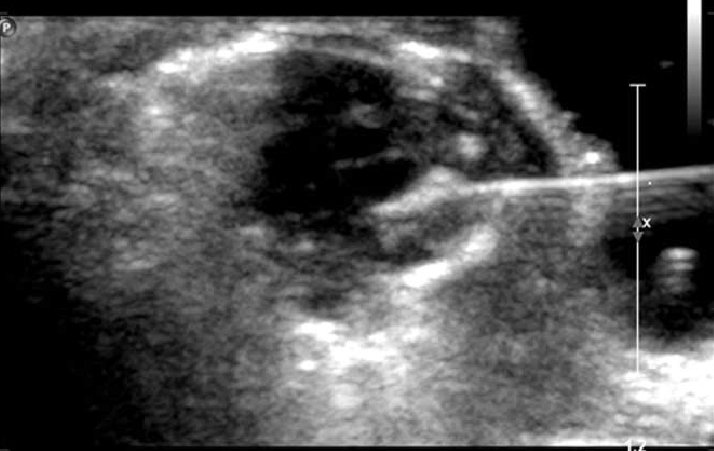

Κάτω από υπερηχογραφικό έλεγχο εισάγουμε λεπτή βελόνη δια μέσου της κοιλιάς της μητέρας στο σάκο της κύησης και εγχύουμε χλωριούχο κάλιο στο έμβρυο που θέλουμε να μειώσουμε.